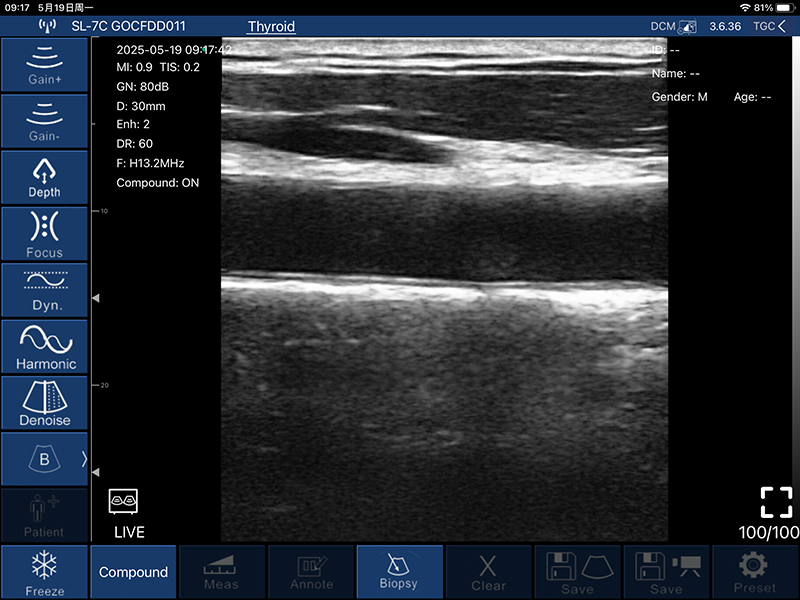

• 扫描深度:20/30/40/60mm,可调

• B模式

增益:30db-105db

降噪:0-1-2-3-4

动态范围: 40-50-60-70-80-90-100-110

• 图像调节:增益、焦点、

反相脉冲谐波、降噪

• 穿刺辅助功能:平面内穿刺引导线功能,平面外穿刺引导与血管自动测量功能